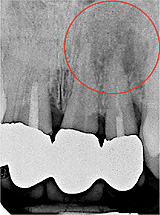

Zweitbehandlung (Revision)

Sollten nach einer bereits durchgeführten Wurzelbehandlung noch Keime im Zahn zurück bleiben, z. B. durch nicht aufbereitete Wurzelkanäle oder nicht vollständig gereinigte Wurzelkanäle, dann können diese später eine chronische, aber auch eine akute Entzündung an der Wurzelspitze auslösen.

In diesem Fall sollte eine erneute Behandlung (Revision) durchgeführt werden. Der Ablauf entspricht dem oben beschriebenen, zusätzlich wird die bestehende Wurzelfüllung entfernt und die Aufbereitung und Reinigung der Wurzelkanäle wiederholt.

Oberkieferschneidezähne mit z. T. unvollständiger Wurzelfüllung und chronischer Entzündung an den Wurzelspitzen und Ausheilung nach 11 Monaten